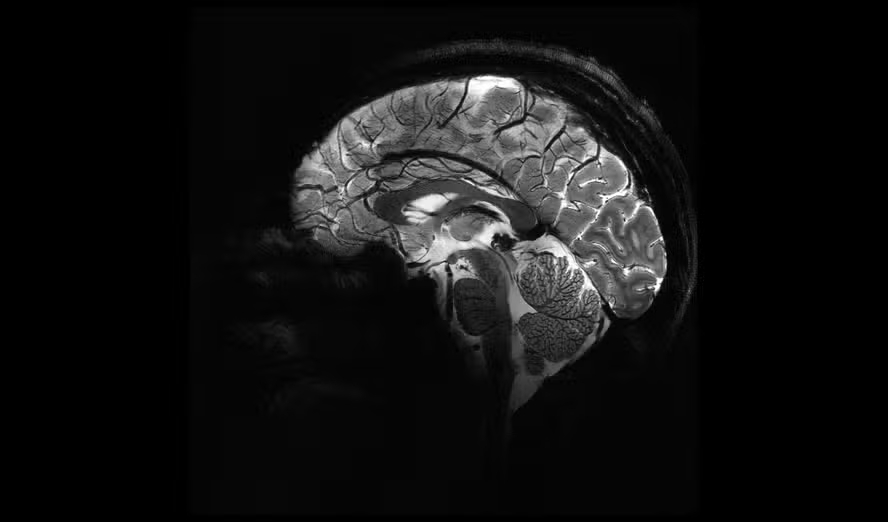

Foto: Divulgação / Comissão de Energia Atômica da França (CEA)

O scanner de ressonância magnética mais poderoso do mundo forneceu as primeiras imagens de cérebros humanos, atingindo um novo nível de precisão que, para os especialistas, pode lançar luz sobre os mistérios das mentes — e as doenças que as assombram.

Vista axial do cérebro humano, com o mesmo tempo de aquisição, mas com diferentes intensidades de campo magnético. Na última, a imagem do Iseult Magneton 11.7 T MRI. — Foto: Divulgação / Comissão de Energia Atômica da França (CEA)Vista axial do cérebro humano, com o mesmo tempo de aquisição, mas com diferentes intensidades de campo magnético. Na última, a imagem do Iseult Magneton 11.7 T MRI. — Foto: Divulgação / Comissão de Energia Atômica da França (CEA)

O campo magnético criado pelo scanner é de impressionantes 11,7 teslas, uma unidade de medida que leva o nome do inventor Nikola Tesla.

Essa potência permite que o aparelho escaneie imagens com 10 vezes mais precisão do que as ressonâncias magnéticas comumente utilizadas em hospitais, cuja potência normalmente não ultrapassa três teslas.

Na tela do computador, Vignaud comparou imagens obtidas por esse poderoso scanner, apelidado de Iseult, com imagens de uma ressonância magnética normal.

— Com esta máquina podemos ver os minúsculos vasos que alimentam o córtex cerebral, ou detalhes do cerebelo que eram quase invisíveis até agora — explica ele.